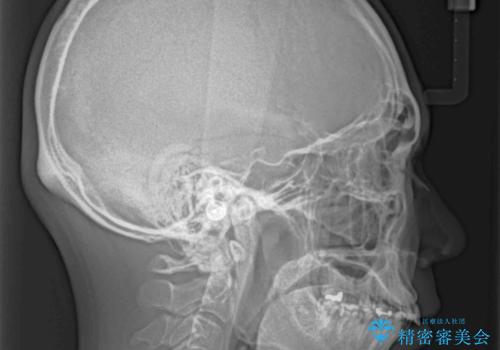

- 深い咬み合わせと前歯のデコボコ、奥歯の欠損を気にして来院された患者様です。

歯列矯正はインビザラインを使用し、矯正治療中の適切な時期に奥歯の欠損部位にインプラントを埋入することとしました。